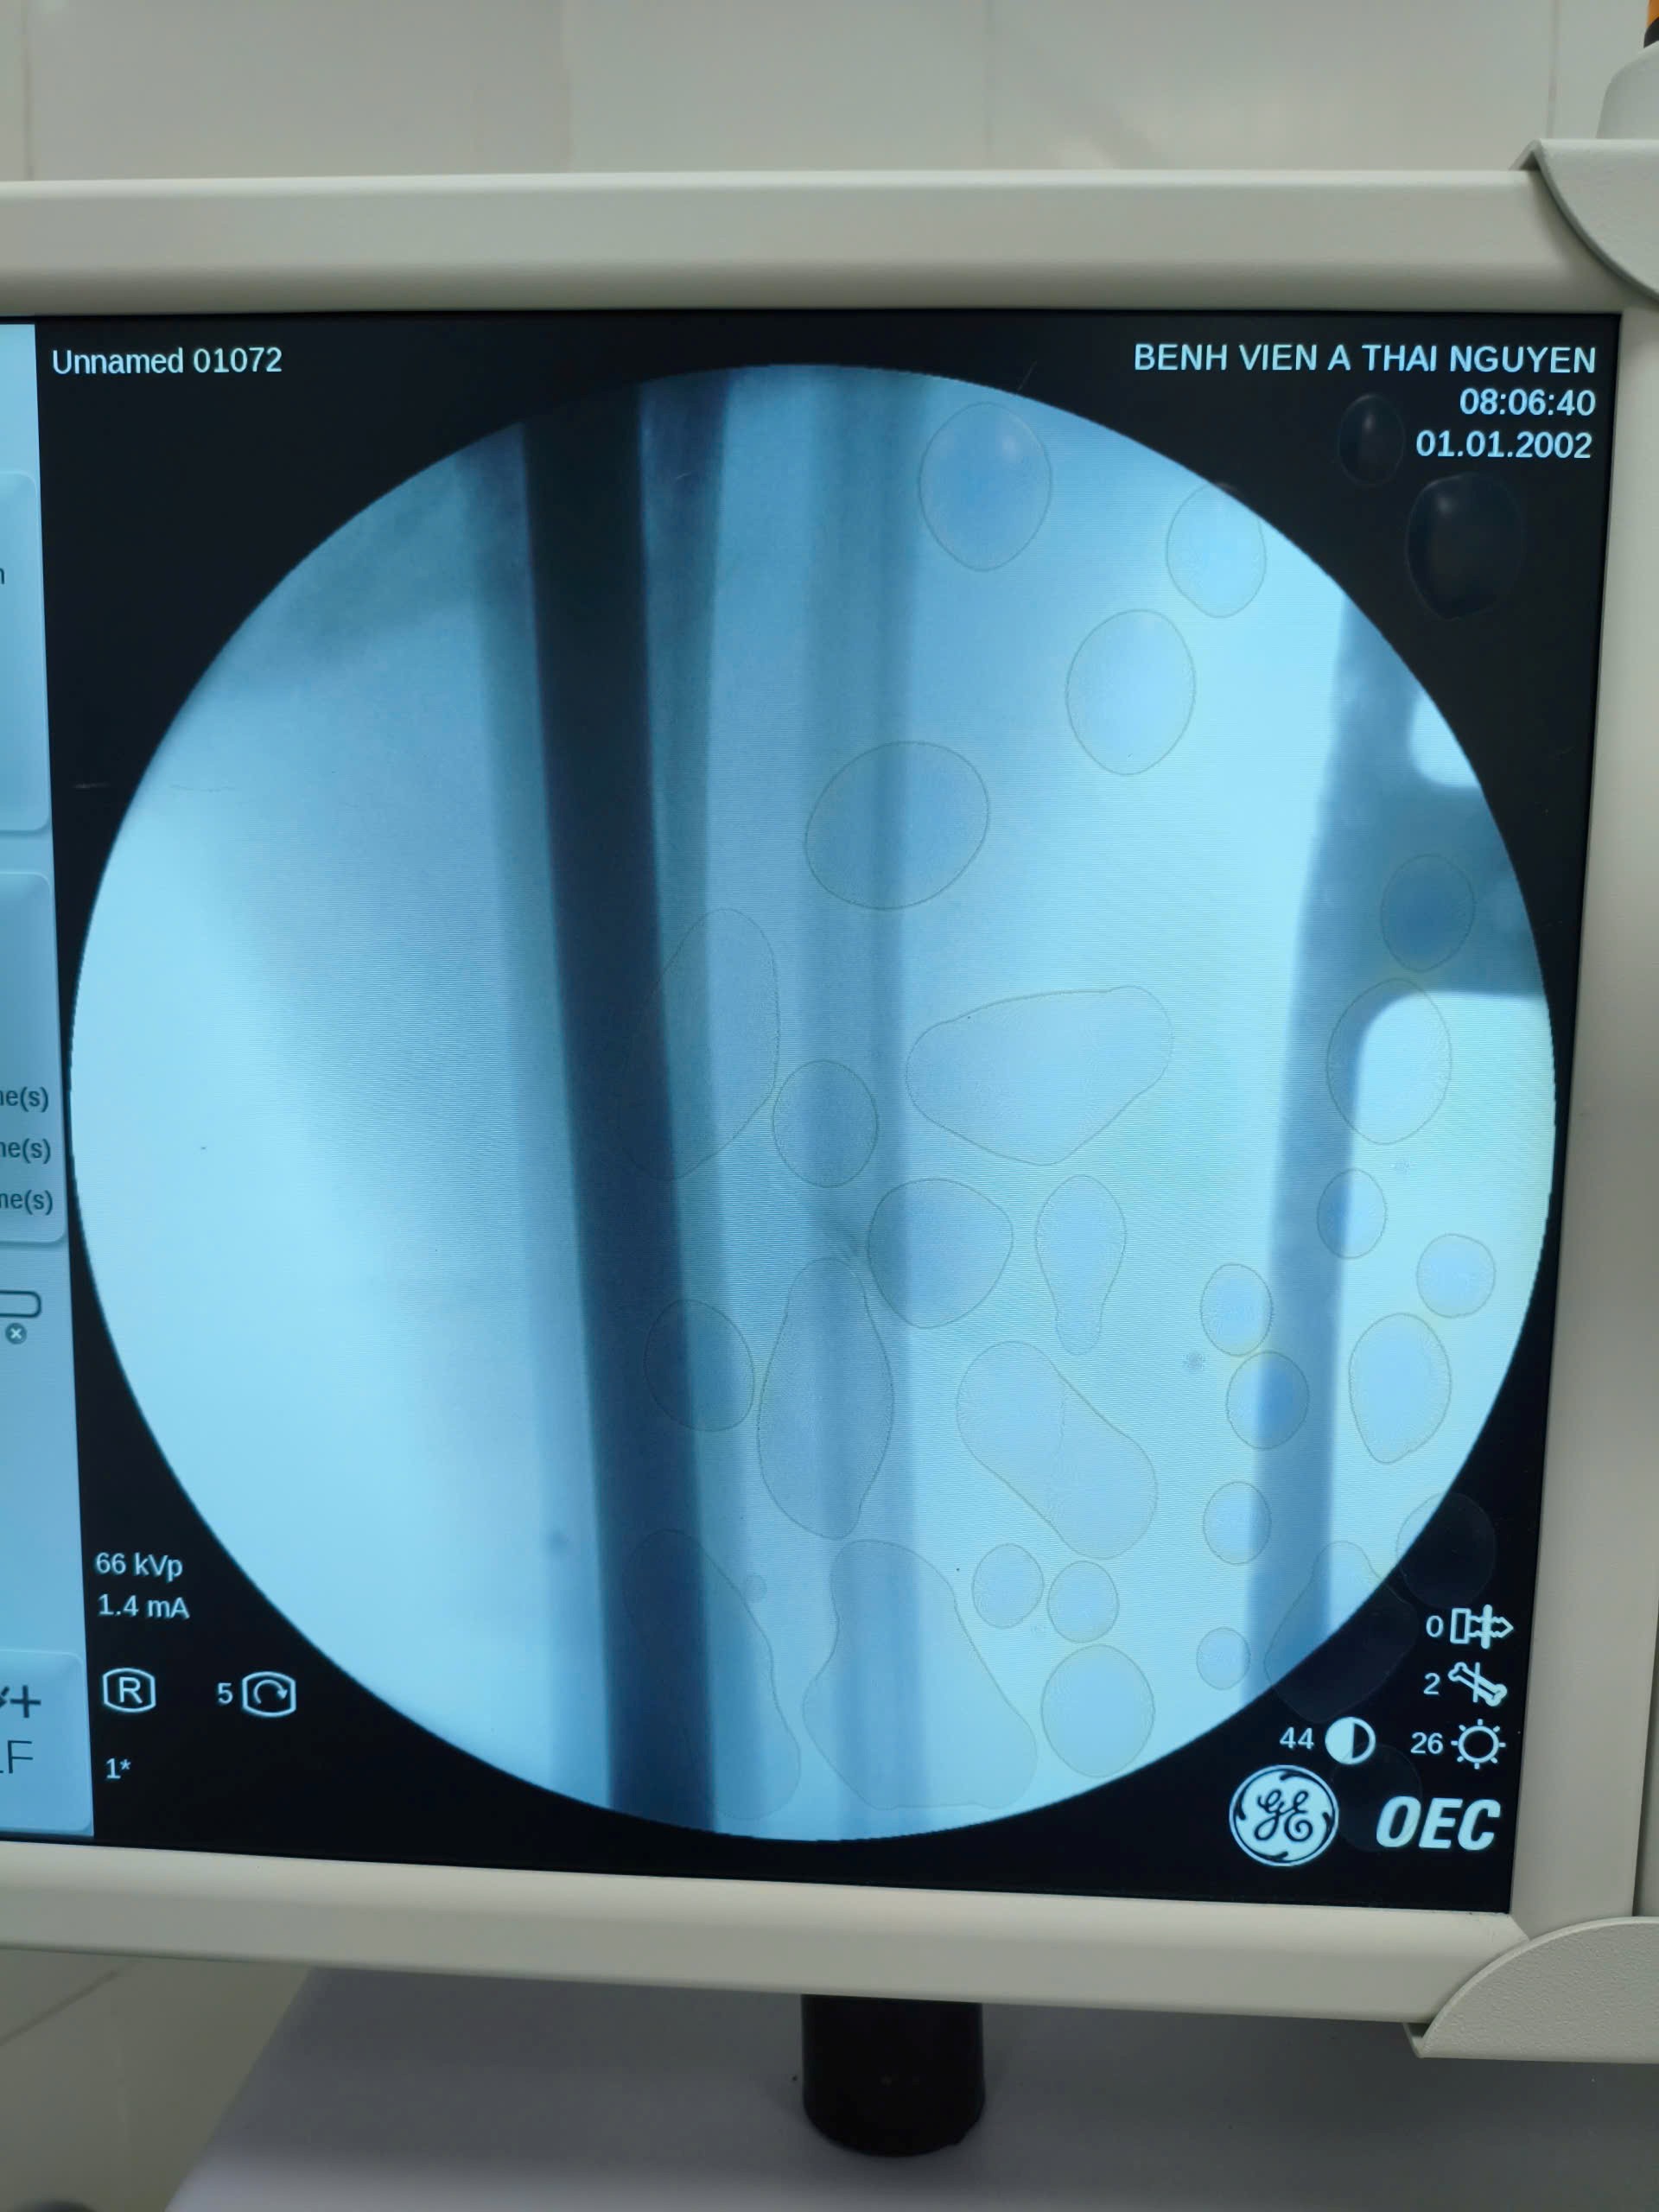

Hình ảnh X-quang bệnh nhân nữ 19 tuổi, gãy 1/3 giữa hai xương cẳng chân phải do tai nạn giao thông.